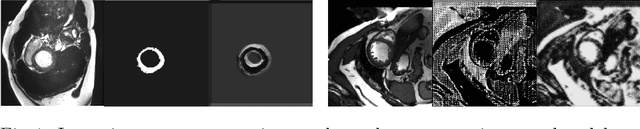

Abstract:The success and generalisation of deep learning algorithms heavily depend on learning good feature representations. In medical imaging this entails representing anatomical information, as well as properties related to the specific imaging setting. Anatomical information is required to perform further analysis, whereas imaging information is key to disentangle scanner variability and potential artefacts. The ability to factorise these would allow for training algorithms only on the relevant information according to the task. To date, such factorisation has not been attempted. In this paper, we propose a methodology of latent space factorisation relying on the cycle-consistency principle. As an example application, we consider cardiac MR segmentation, where we separate information related to the myocardium from other features related to imaging and surrounding substructures. We demonstrate the proposed method's utility in a semi-supervised setting: we use very few labelled images together with many unlabelled images to train a myocardium segmentation neural network. Specifically, we achieve comparable performance to fully supervised networks using a fraction of labelled images in experiments on ACDC and a dataset from Edinburgh Imaging Facility QMRI. Code will be made available at https://github.com/agis85/spatial_factorisation.